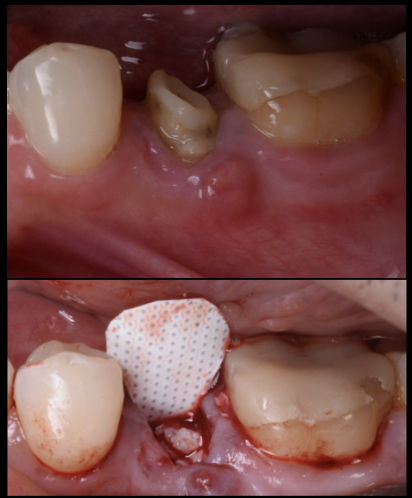

【グランドメゾンデンタルクリニック】抜歯後の骨...